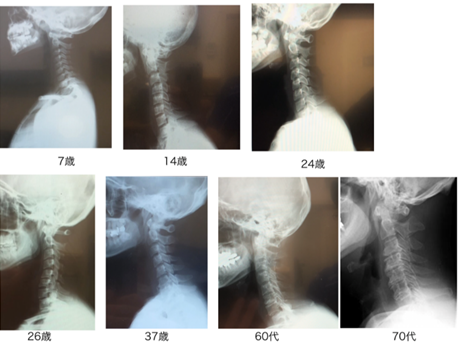

姿勢により脊柱の違いがわかる

上記の写真をみてください。

子どもは前屈時に脊柱のキレイな弯曲がみられます。

しかし、大人の前屈では脊柱が子どもと同じ形状をしていません。

背中の真ん中がボコっと出ているのがわかると思います。

脊柱が過剰に曲がっているのです。

腰も子供と比べると丸みはなく、真っ平らになります。

子供とでは脊柱の形が違う